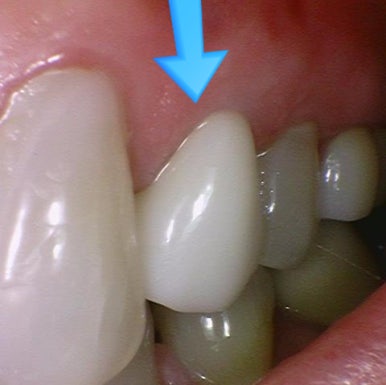

연세예감치과 지르코니아 크라운 전 후 (화살표치아)